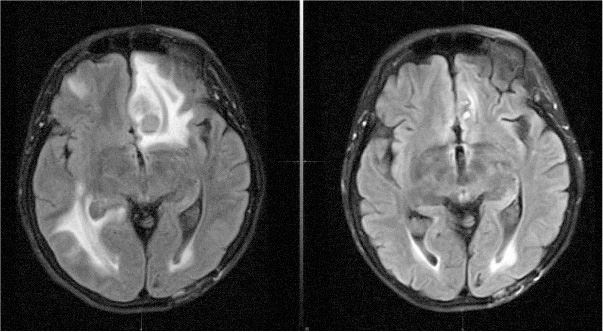

Иллюстрация к книге — Потерявшая разум. Откровенная история нейроученого о болезни, надежде и возвращении [i_009.jpg]

Снимки моего мозга 19 июня (слева) и 21 июля (справа). Отек (светлые области на снимке) заметно спал, и опухоли, включая самую крупную во фронтальной коре, исчезли

Доктор Аткинс предложил нам посмотреть новый снимок на своем компьютере. Кася разглядывала его в изумлении.

– Невероятно! – воскликнула она. – Почти все опухоли пропали!